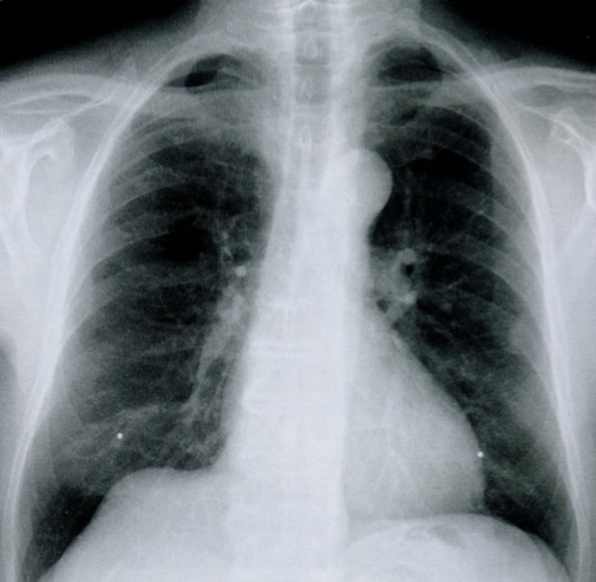

Оцените костные структуры, отмеченные стрелками.

Какие возрастные особенности реберного каркаса могут встречаться на снимках?

На снимке отмечены реберные дуги, что очевидно. Мы видим четкие верхние и нижние края ребер, при этом картинка может быть менее четкая в нижних и средних отделах грудной клетки, что считается нормой (зависит от хода рентгеновских лучей, так как картинка становится более четкой, когда луч проходит край ребра по касательной).

У лиц старше 15 лет в области костно-хрящевого соединения отмечаются обызвествления различной степени выраженности (стрелки на снимках). Обычно они симметричны и чаще встречаются у женщин, чем у мужчин.